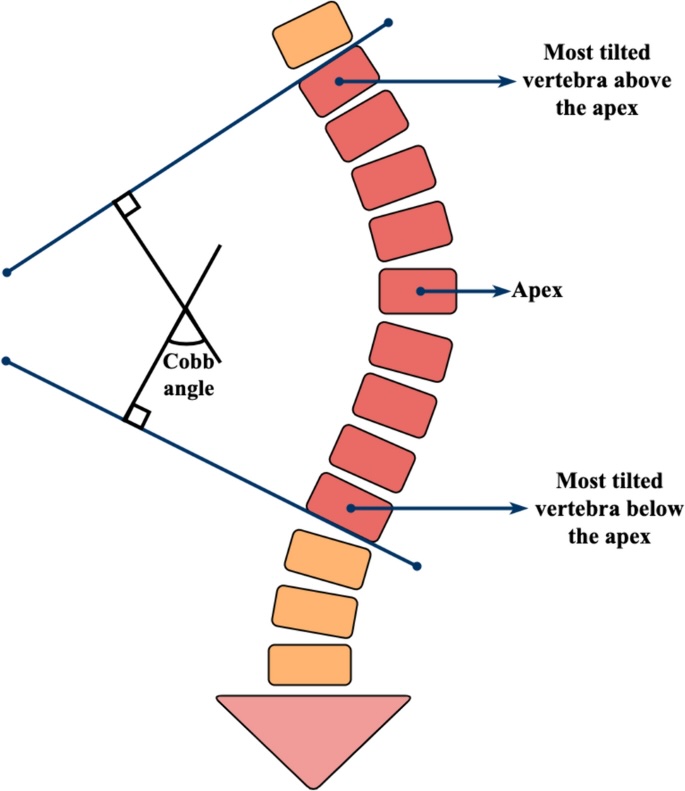

Scoliose mesurant ° entre le plateau supérieur de et le plateau inférieur de .

Stade d'ossification Risser

Bascule du bassin par dénivelation vers la

Absence de malformation ou de lésion vertébrale décelable.

mauvais Pc si > 30°

mauvais Pc si > 30°

degré rotation vertébrale selon Cobb en fonction de l'épineuse

degré rotation vertébrale selon Cobb en fonction de l'épineuse

déséquilibre frontal (fil à plomb électronique centré sur T1)

déséquilibre frontal (fil à plomb électronique centré sur T1)

bascule du bassin (axe du pleateau supérieur de S1)

cyphose thoracique - lordose lombaire (T4 - vertèbre jonctionnelle - S1)

pente sacrée et incidence pelvienne

évolution à la puberté jusqu'à Risser 3

évolution à la puberté jusqu'à Risser 3

(Risser 1 à 13-14 ans pour les filles et 15-16 ans pour les garçons)